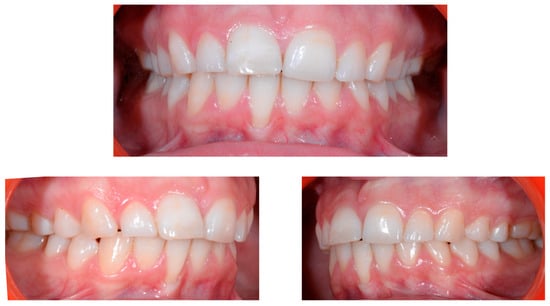

A 22-year-old female patient in good health had a consultation because she was concerned about the “root prominence” of tooth 41. She wore a mandibular retainer wire when she was 16 years old at the end of her orthodontic treatment. She has good oral hygiene, despite the presence of tartar between 31 and 41, and a right and left Class I with a slight deviation of the midlines (Figure 1).

Figure 1.

Early wire syndrome. Frontal and lateral views.

In Figure 2, the following can be observed: a difference in gingival margin height between 41 and 31, a difference in height of the incisal edges of 41 compared to the adjacent teeth, and the onset of gingival recession on 41 associated with the visibility of a vestibular arch corresponding to its root.

Figure 2.

Early wire syndrome. Frontal views.

In the lateral view (Figure 3), the prominence of the root of 41 was confirmed.

Figure 3.

Early wire syndrome. Lateral view.